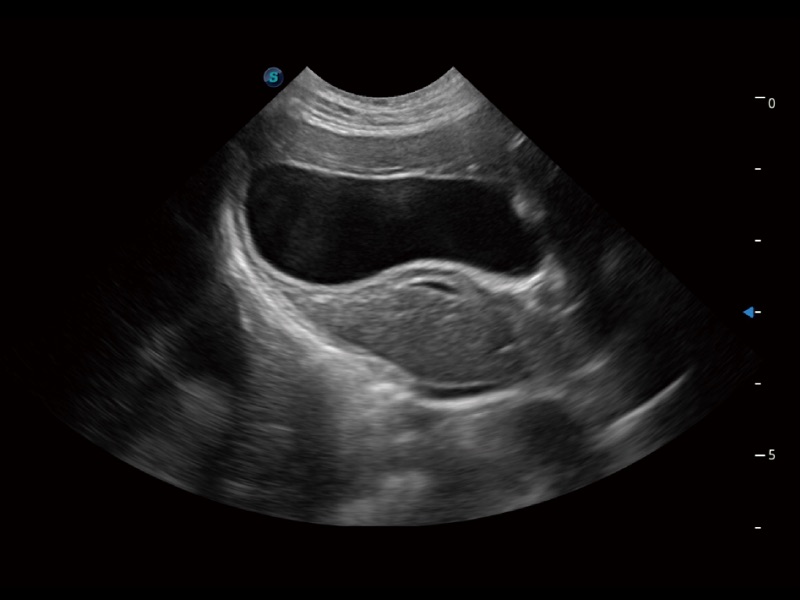

优异的基础图像

(犬)肾脏显微血流